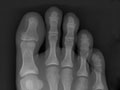

While X-rays of extremities (hands and feet) are sometimes useful in the late stages of the disease, X-rays aren't usually helpful in the early diagnosis. Pain often causes people to seek medical attention before any long-term changes can be seen on an X-ray. But X-rays may help to rule out other causes of arthritis.